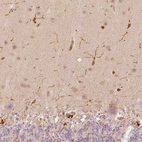

Immunohistochemical staining of human cerebellum, cerebral cortex, testis and tonsil using Anti-FSCN1 antibody HPA005723 (A) shows similar protein distribution across tissues to independent antibody HPA050654 (B).